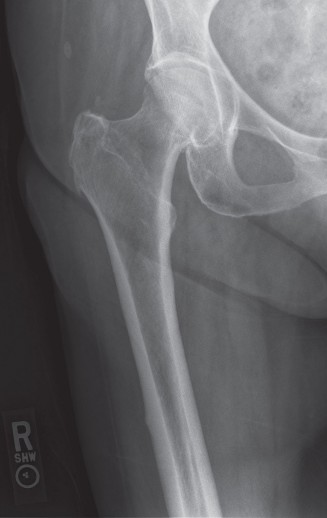

Image